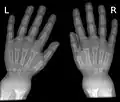

Les atteintes des membres sont les plus caractéristiques. Les bourrelets ou renflements osseux sont d'abord palpables au poignet, bord externe du radius (précoce), et à la cheville (au-dessus de la pointe de la malléole externe), puis visibles.

La radiologie confirme le diagnostic, et il est inutile de les multiplier. Le défaut de minéralisation des os longs s'observe particulièrement sur les radiographies de face d'un poignet et des genoux : retard ou irrégularités des points d'ossifications attendus pour l'âge (maturation squelettique), lignes métaphysaires irrégulières donnant un aspect « en toit de pagode », la corticale de la diaphyse est amincie, la densité osseuse est diminuée donnant un aspect vermoulu. Les os longs s'incurvent.

Radiographie de mains et poignets.